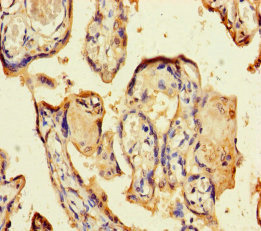

CSF2作為一種重要的細胞因子,在免疫調節、炎癥反應和腫瘤進展中發揮著關鍵作用。通過深入研究CSF2的作用機制和相關信號通路,可以為多種疾病的治療提供新的靶點和策略。華美生物重磅推出多款高活性的CSF2蛋白產品,并提供CSF2抗體及ELISA試劑盒產品,助力您在CSF2機制方面的研究或其潛在臨床價值的探索。

● CSF2 / GM-CSF Recombinant Proteins

● CSF2 / GM-CSF Antibodies

● CSF2 / GM-CSF ELISA Kits